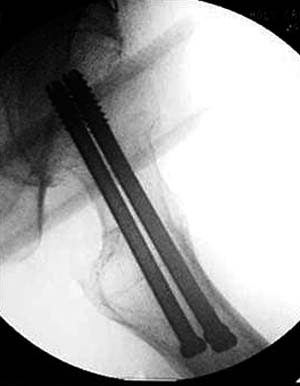

Правильная техника фиксации - это три параллельных  каннюлированных винта под углом 130 -135 градусов к диафизу, не ниже уровня малого вертеля. Проведенные ниже вертела винты с бОльшим углом (более вертикальные) в 20% осложнялись подвертельными переломами бедра. Ближе к кортикальному слою винты с длинным контактом резбовой части, а также каннюлирванные механически лучше, чем сплошные. Расположение винтово - в  в виде V т.е. один внизу по калькару и два сверху-спереди и сзади.

Вложение не в текстовом формате было извлечено…

Имя     : 2 Fem neck intraop lat.jpg

Тип     : image/jpg

Размер  : 24335 байтов

Описание: отсутствует

Url     : http://weborto.net:8080/pipermail/ortho/attachments/20120118/c4b77b39/attachment-0006.jpg